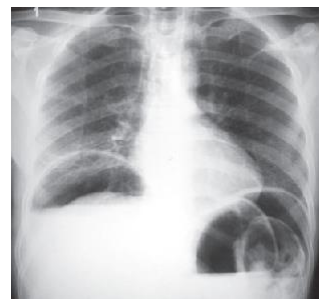

Uma paciente de 45 anos deu entrada no pronto-socorro com quadro de dor torácica aguda, pleurítica, aliviada na posição sentada com inclinação corporal anterior e piora com inspiração profunda. Teve quadro de febre e mialgia 24 horas antes do início da dor torácica.

Foi realizado ECG representado na imagem abaixo.

Considerando os dados apresentados, o diagnóstico mais provável para o caso acima é: